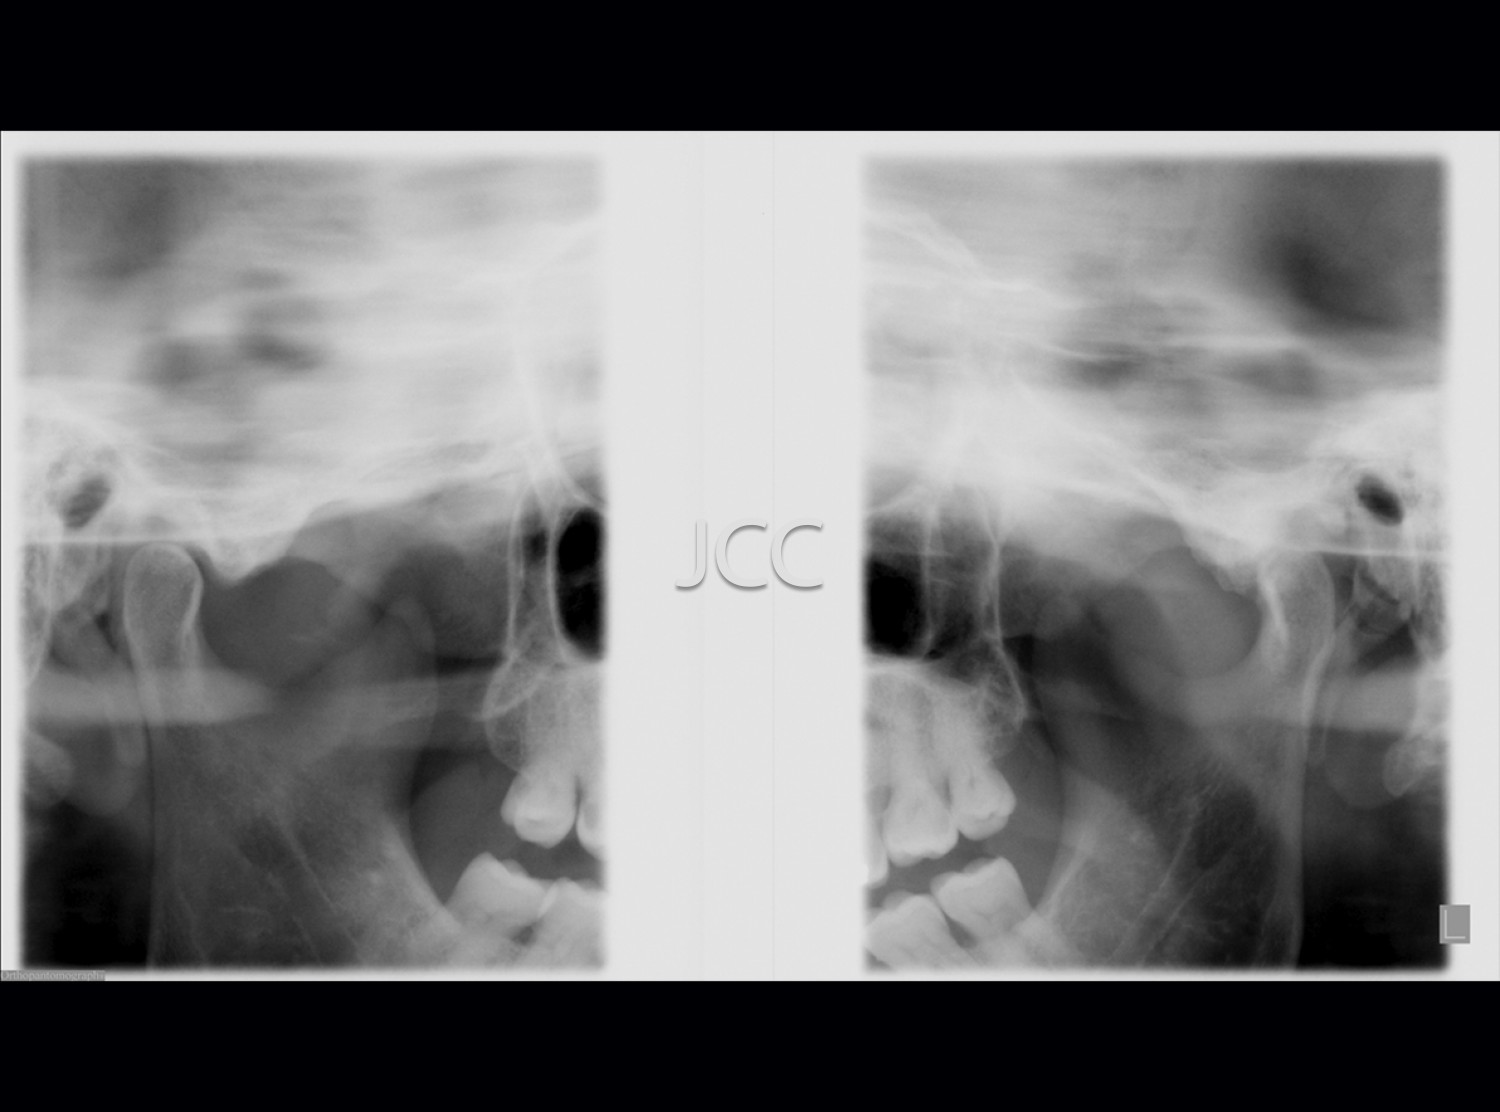

Dental Radiology - TMJ X-ray